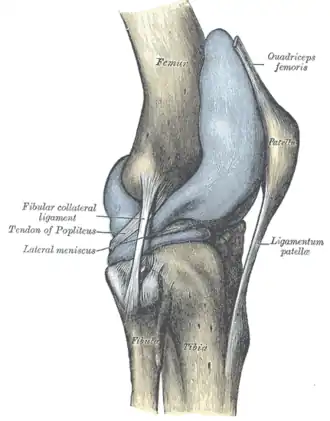

Ligamentos

Nome Cápsula Origem Inserção Descrição

ligamento cruzado anterior (LCA) dentro côndilo lateral do fêmur área intercondilar anterior O papel do LCA é prevenir o deslizamento anterior excessivo da tíbia em relação ao fêmur

ligamento cruzado posterior (LCP) dentro côndilo medial do fêmur área intercondilar posterior A lesão deste ligamento é incomum, mas pode ocorrer resultando de uma força de tração traumática do ligamento. Este ligamento previne o deslizamento posterior excessivo da tíbia em relação ao fêmur.

ligamento capsular - - - -

ligamento patelar fora patela tuberosidade da tíbia - Também Chamado de Tendão Patelar pelo motivo de nao existir uma separação definida entre o tendao do quadriceps (o qual envolve a patela) e a area conectando a patela à tibia. Este forte ligamento ajuda no mecanismo de alavanca da patela e também funciona como tampão para os côndilos femorais.

ligamento colateral medial ou ligamento colateral tibial (LCM) fora epicôndilo medial do fêmur condilo tibial medial O Ligamento Colateral Medial protege a parte medial do joelho de ser aberto por uma força aplicada nas laterais do joelho (joelho valgo).

ligamento colateral lateral ou ligamento colateral fibular (LCL) fora epicôndilo lateral do fêmur cabeça da fíbula o Ligamento Colateral Lateral protege as laterais do joelho de uma força dobrante interior (joelho varo).

ligamento poplíteo oblíquo fora côndilo externo do fémur continuidade do tendão do semimembranoso Expansão Tendinosa dos musculo semimembranoso. Fortalece a parte de trás da capsula

ligamento poplíteo arqueado fora área intercondilar da tíbia côndilo lateral do fêmur a seguir da cabeça fibular Conecta para a porção medial da cabeça fibular Este ligamento fortalece o joelho posterolateralmente e quando lesionado está em combinação com uma lesão do tendão PCL e poplítea.